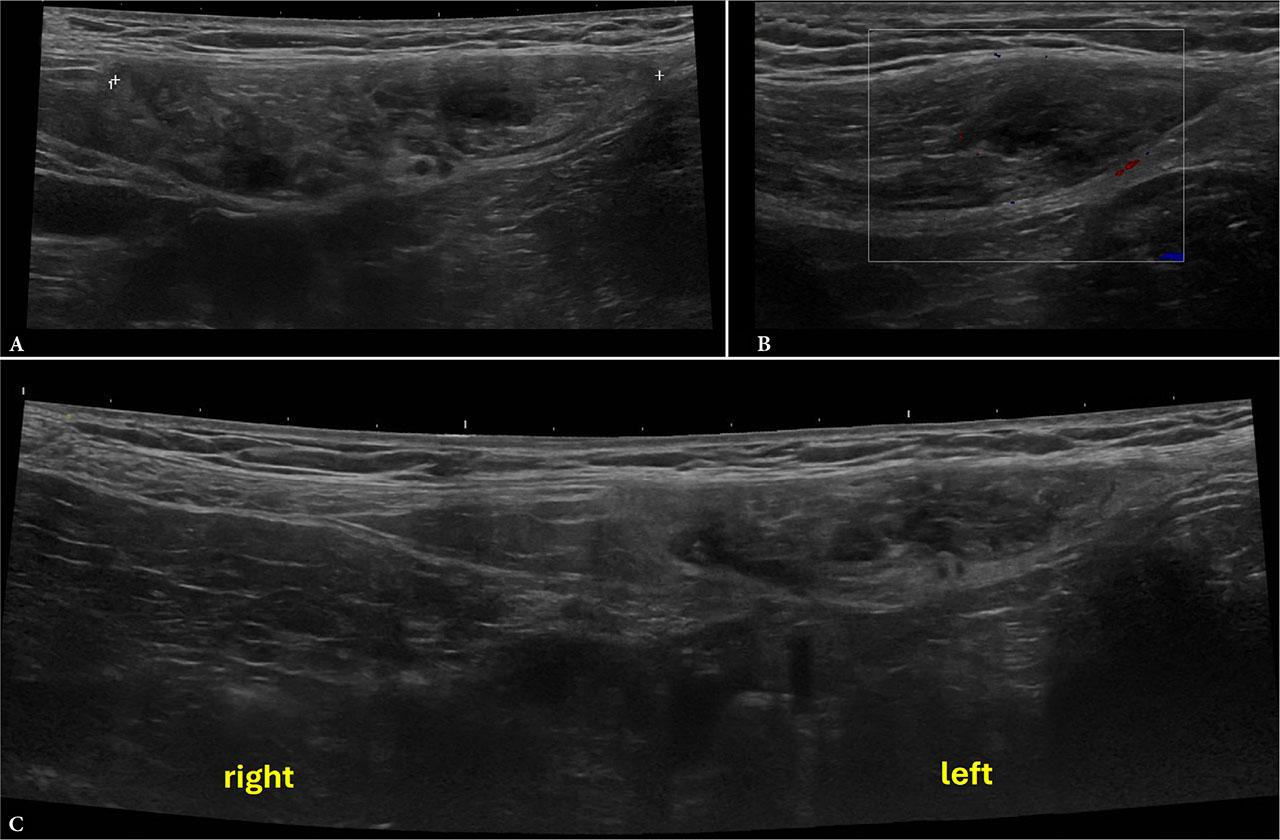

Given the patient’s underlying hematological condition and the localized nature of the symptoms, an urgent US examination of the abdominal wall was performed. The US demonstrated focal thickening and heterogeneity of the left rectus abdominis muscle with multiple small anechoic foci, consistent with an intramuscular hematoma (Fig. 1).

Ultrasound of the left rectus abdominis muscle demonstrating intramuscular thickening (6.8 × 1.6 cm) with heterogeneous hypoechoic areas (A) and no internal flow on CD (B), consistent with an intramuscular hematoma. Comparative imaging (C) confirms asymmetry relative to the contralateral side

Educational tip: Use bilateral comparative scanning to identify asymmetry in muscle thickness and echotexture. The absence of internal color Doppler (CD) signal is a key feature that supports the diagnosis of hematoma rather than neoplasia or abscess.

Clinical correlation: In thalassemia, factors such as iron overload, liver dysfunction, and platelet abnormalities increase bleeding risk. This explains the occurrence of spontaneous hematoma in the absence of trauma or anticoagulant therapy(11,12).